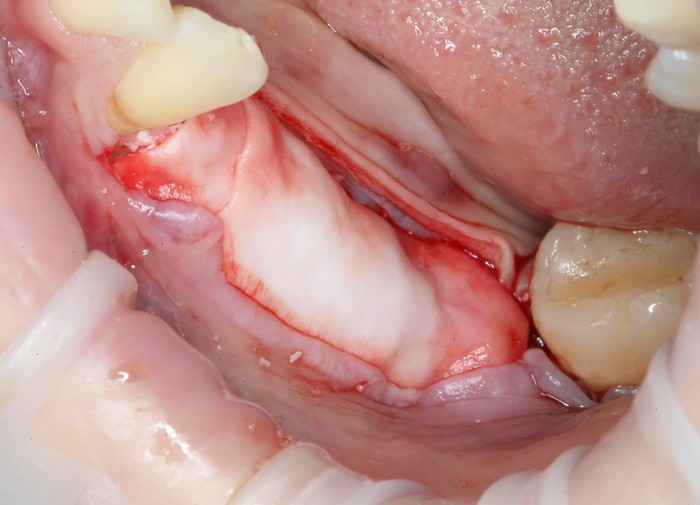

На верхней челюсти было дополнительно удалено два боковых резца с одномоментной установкой имплантатов, так же они были установлены в области четверок и шестых зубов. Дополнительно было проведено наращивание костной ткани - двусторонний синус - лифтинг. О том, что это такое, можно почитать ТУТ и ТУТ.

После нехитрых манипуляций мы прощаемся с Русланом на 4 месяца.

Этого времени достаточно на приживление имплантатов.